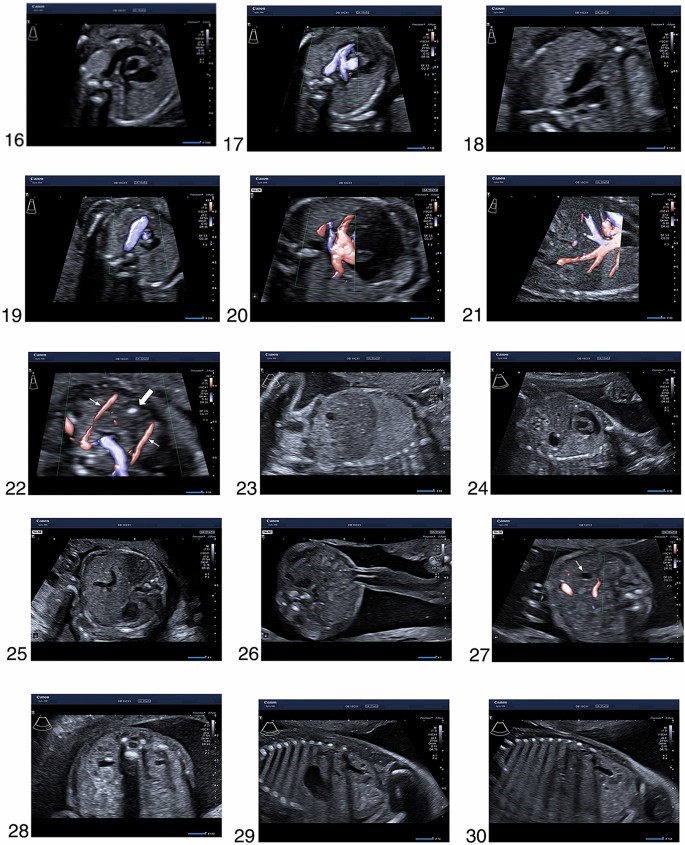

مجموعه تصاویر محصور شده در شرایط ایده آل در بیماران با شاخص توده بدنی پایین، جنین در وضعیت مطلوب، مایع آمنیوتیک طبیعی، بدون فیبروم و بدون ناهنجاری رحمی به دست آمد. آنها همچنین در یک سری از بیماران به دست می آیند. بنابراین، ما اذعان داریم که در عمل بالینی روزمره، ممکن است با موقعیتهایی مواجه شویم که در آن به دست آوردن تصاویر با چنین کیفیتی امکانپذیر نباشد. با این حال، هر تلاشی باید برای نشان دادن تمام ساختارهای مربوطه انجام شود. اگر این امکان وجود ندارد، ممکن است لازم باشد جنین را به آرامی با دست دیگر حرکت دهید، از بیمار بخواهید به پهلو بچرخد، بیمار را به پیاده روی بفرستد و مثانه را خالی کند یا در نهایت بیمار را برای 2 هفته مجدد رزرو کنید. بعدا برای یک معاینه سونوگرافی دقیق دیگر. هر محدودیتی که بر کیفیت تصویر تأثیر می گذارد باید در گزارش ذکر شود .

- تصویر عرضی دور سر در سطح قطر دو جداری، با خط وسط فالک، سپتی کائویی، تالامی و بطن جانبی

- حفره خلفی مغز با مخچه و سیسترنا میگنا

- صفحه تاجی سر جنین

- نیمرخ جنین ساژیتال وسط

- صفحه تاجی لب ها با لب بالایی، دهان سالم، لب پایین و بینی

- مدارها با لنز

- کام سخت

- صفحه عرضی گردن با غده تیروئید

- تصویر ساژیتال گردن

- تصویر ساژیتال ستون فقرات با خطوط دست نخورده پوست

- عرضی صفحات بالای شکم با معده و قفسه سینه با چهار حفره قلب

- تصویر عرضی قفسه سینه با نمای اپیکال چهار حفره ای قلب و ریه ها

- نمای آپیکال چهار محفظه t قلب در داپلر رنگی

- مجرای خروجی بطن چپ

- مجرای خروجی بطن چپ در داپلر رنگی

- مجرای خروجی بطن راست

- مجرای خروجی بطن راست در داپلر رنگی

- نمای سه رگ

- نمای سه رگ در داپلر رنگی

- وریدهای ریوی در داپلر رنگی

- ورید اجوف تحتانی در داپلر رنگی

- تیموس (فلش بلوکی) بین دو شریان پستانی داخلی

- تصویر بدن پارا ساژیتال با دیافراگم راست

- تصویر بدن پارا ساژیتال با دیافراگم چپ

- تصویر عرضی دور شکم با معده در وضعیت طبیعی

- قرار دادن بند ناف با دیواره شکم دست نخورده

- کیسه صفرا

Tuebingen), 28. صفحه عرضی کلیه ها که هر دو لگن کلیه را نشان می دهند

- نمای ساژیتال کلیه چپ

- نمای ساژیتال کلیه راست

- مثانه با هر دو شریان نافی

- استخوان ران

- نمای جلویی ساق پا با استخوان درشت نی و پرونئوس

- ساق با درشت نی و زاویه صحیح مفصل تالوکرال

- پا (*، + ،#)، 36. شانه و بازو

- ساعد با شعاع و اولنا

- دست

39 نمای ترانس شکمی دهانه رحم

- جاگذاری جفت بند ناف

- شریان رحمی